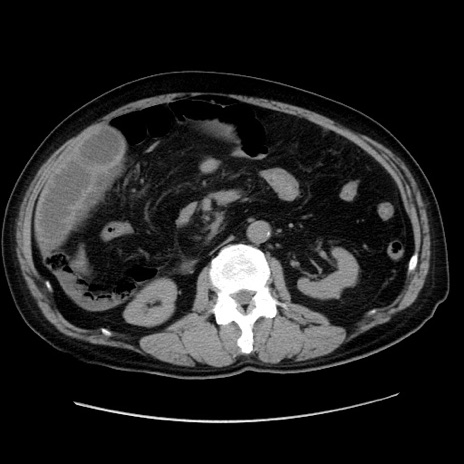

症例30(横断像)

【症例】80歳代男性

【主訴】臍周囲痛

【現病歴】約6時間前から臍下部痛が出現。次第に腹部膨隆・背部痛も生じてきたため来院。背部痛の場所は変化しない。

【既往歴】腎盂腎炎

【身体所見】意識清明、BT 36.3℃、BP  131/87mmHg、P 87bpm、SpO2 100%(RA)、臍周囲自発痛・圧痛あり、反跳痛なし、自発痛部位に一致して板状硬あり、腹部膨隆、腸雑音減弱、CVA tenderness両側陰性。

【データ】WBC 19600、CRP 0.33